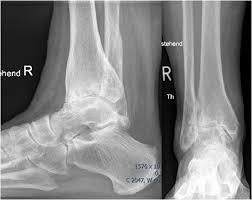

Диагностика и лечение

Для точного определения причины боли проводится осмотр, рентгенография, УЗИ или МРТ. В зависимости от диагноза назначается лечение — иммобилизация, физиотерапия, медикаментозная терапия или хирургическое восстановление связок. При воспалительных заболеваниях применяются противовоспалительные препараты и процедуры, направленные на улучшение кровообращения и восстановление функции сустава.